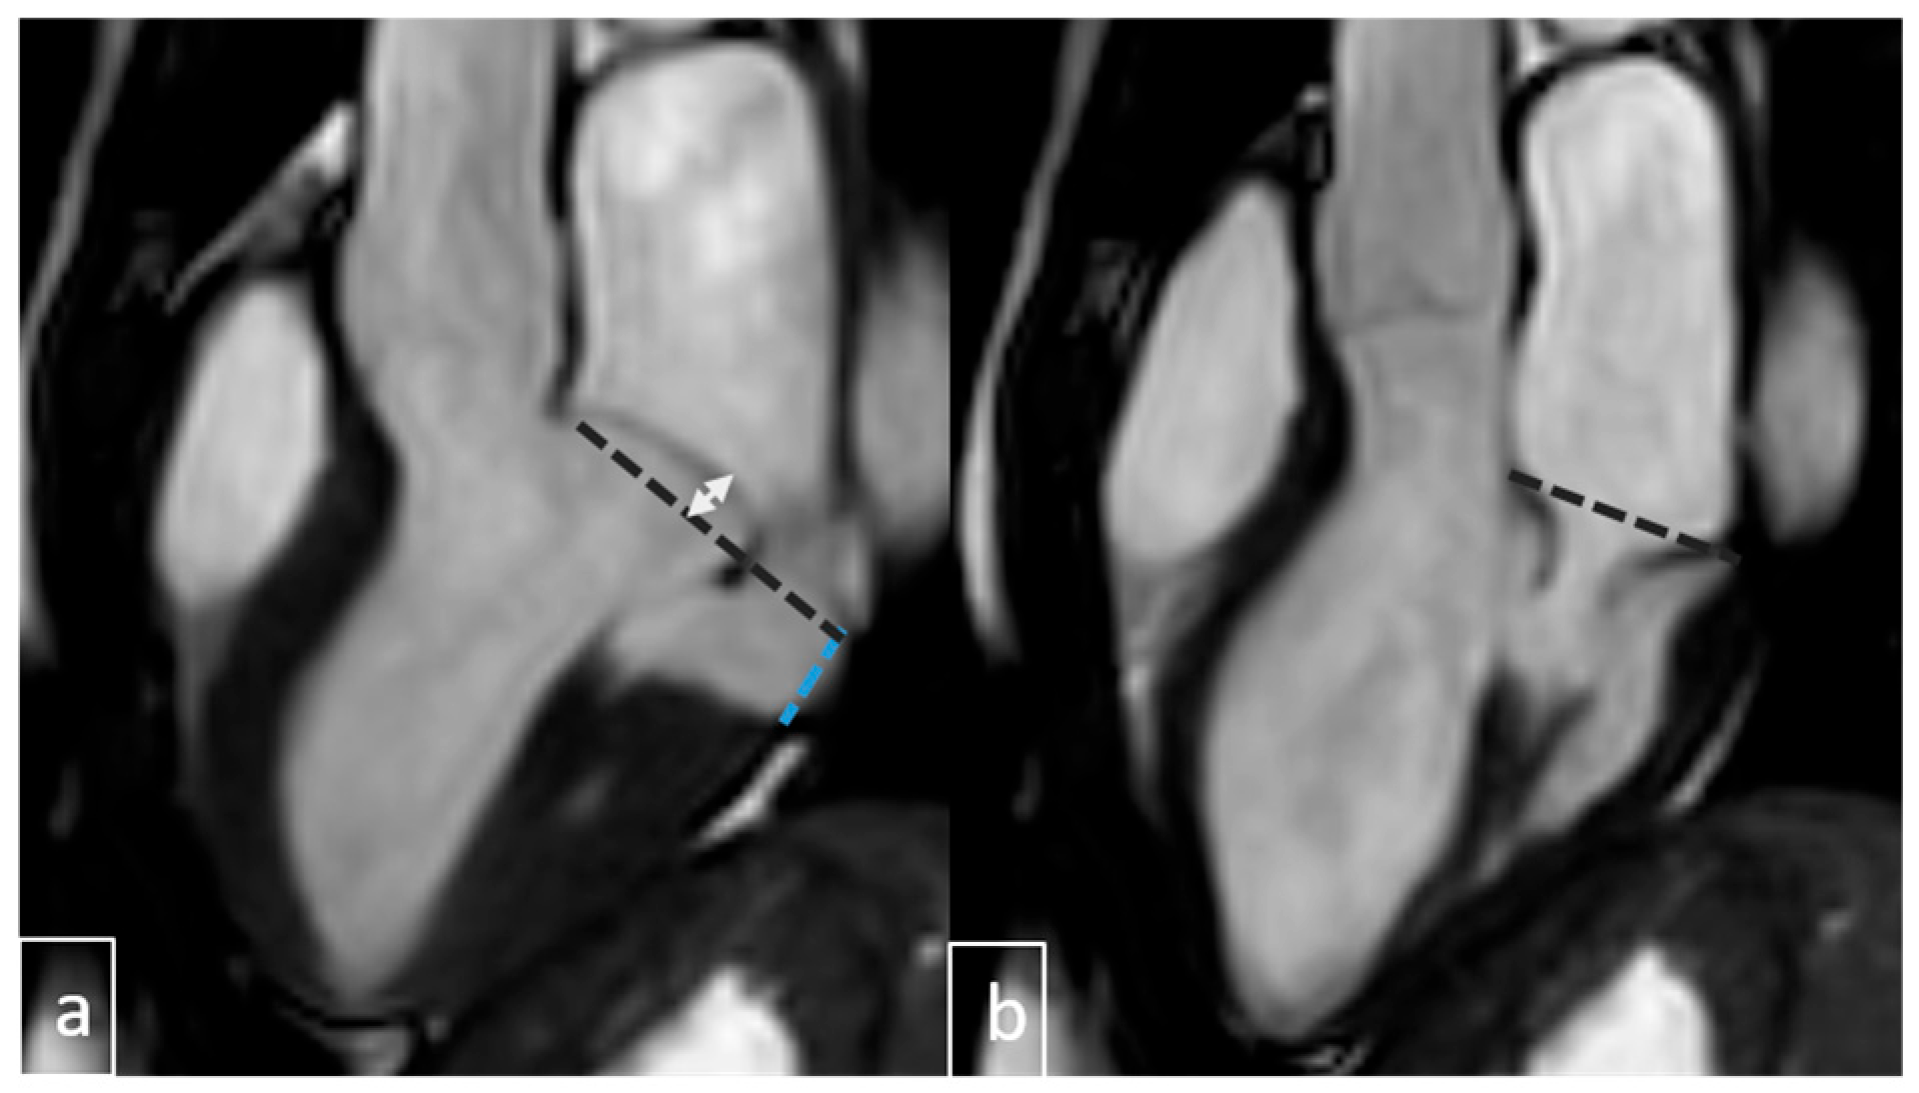

2.4. Image Analysis